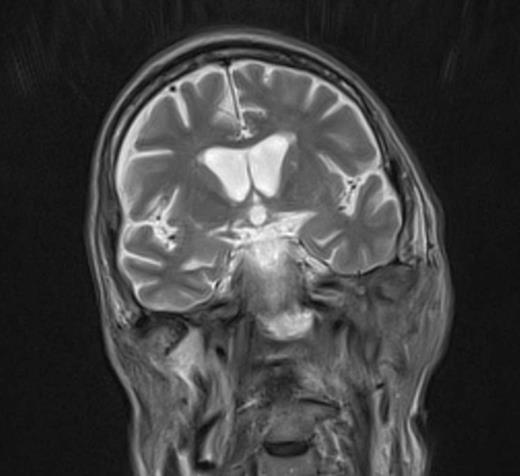

At the tertiary hospital the patient was found to be clinically wasted and weak. He also had rightward uvular deviation, absent gag reflex, weakness of the left sternocleidomastoid and trapezius, House Brackman grade 2 left facial nerve weakness and an immobile left vocal cord. This was the first time a cranial nerve examination was recorded. MRI and SPECT/CT with Gallium tracer was performed, the images acquired from which illustrate the severe extent of disease (figures 1 to 5).

He was diagnosed with MOE with extensive skull base osteomyelitis producing multiple lower cranial neuropathies. Biopsy performed by ORL/ENT surgeons grew Scedosporium apiospermum and given the extent of the infection a palliative approach was agreed upon with the patient and family.